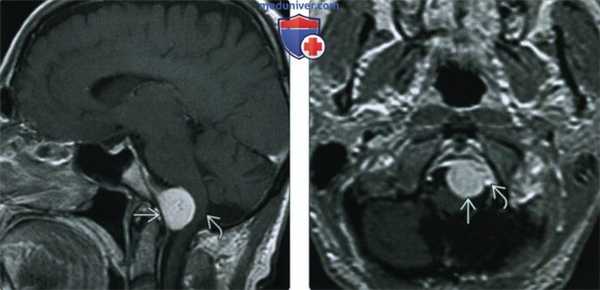

(Слева) При MPT Т1ВИ с КУ в сагиттальной проекции у переднего края большого затылочного отверстия определяется глобулярное объемное образование, смещающее продолговатый мозг кзади. Наличие фиксированного к твердой мозговой оболочке широкого основания свидетельствует в пользу менингиомы, а не какого-либо другого новообразования большого затылочного отверстия, например, шванномы.

(Справа) При МРТ Т1ВИ с КУ в аксиальной проекции определяется менингиома переднего края большого затылочного отверстия, лежащая медиальнее левой позвоночной артерии. Учитывая наличие в основании черепа большого количества критически важных сосудистых и нервных структур, резекция даже небольших новообразований может быть затруднена.

(Слева) МРТ, Т2-ВИ, корональный срез: у мужчины 47 лет определяется внемозговое образование однородной структуры с четкими контурами с минимальным отеком.

(Справа) МРТ, постконтрастное Т1 -ВИ, аксиальный срез: у этого же пациента визуализируется интенсивное относительно однородное контрастное усиление. Обратите внимание на компрессию треугольника левого бокового желудочка. Несмотря на отсутствие агрессивных рентгенологических признаков при хирургической резекции и гистологическом исследовании была диагностирована злокачественная Менингиома grade III. Для окончательного установления гистологического типа и степени злокачественности менингиомы необходима биопсия.

(Слева) МРТ, высокоразрешающее Т2-ВИ, аксиальный срез: у этого же пациента хорошо визуализируется гипоинтенсивное объемное образование с кистозными компонентами и четкими контурами. Гиподенсность указывает на высокое содержание клеточного матрикса в опухоли.

(Справа) МРТ, постконтрастное Т1-ВИ SPGR, корональный срез: контрастное усиление солидных компонентов опухоли. Было выполнено хирургическое удаление, был поставлен гистологический диагноз смеси светлоклеточного (grade II) и склерозирующего вариантов менингиомы.